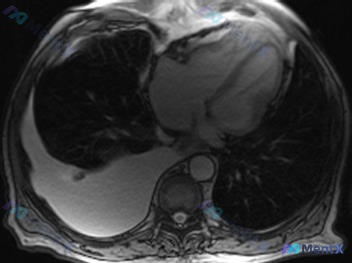

整理了一个挺有启发的病例,我们一起来看看: 基本情况 70岁患者,主要表现是逐渐出现的心力衰竭症状。 关键影像发现 拿到了三张片子:胸部MRI T2、心脏MRI电影和胸部CT。 1. 胸腔积液非常突出:右侧大量,右肺都受压萎陷了,左侧基本干净。 2. 心脏形态有点特别:心脏MRI电影轴位看,左室呈“...